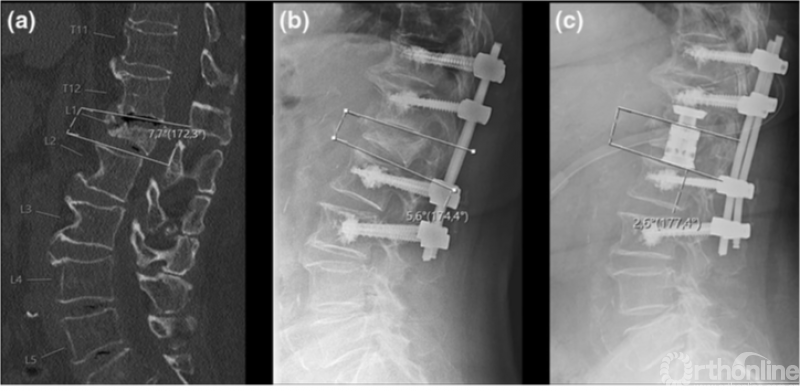

近年来,也有新的治疗技术和观点得以提出,值得探讨。Abhinandan等[7]在Global Spine Journal的文章指出,对于脊柱不稳定而非静态压迫导致的OVCF伴不全瘫患者,行体位复位固定融合手术而不进行椎管减压,可取得良好结果,作者认为OVCF伴不全瘫并非都需要直接减压,部分患者的不全瘫是由不稳定引起,动态MRI是进行准确诊断、制定手术策略的重要依据。

动态MRI检查方法

动态MRI判断脊髓压迫情况